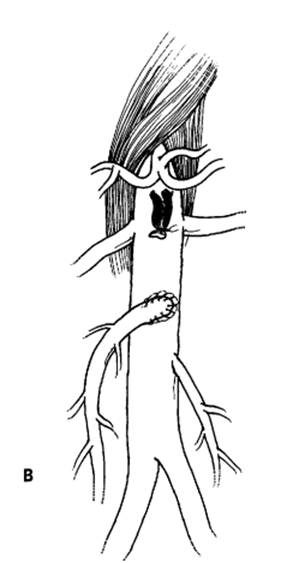

FIG. A - Schematic representation of revascularization of the SMA with: bypass taking care to avoid kinking and obs-

truction B - Or re-implantation of SMA into the aorta. C - Angiographic appearance of aorto-SMA bypass with vein graft.

There is co-existing left common iliac occlusion. D - Angiographic appearance of re-implanted SMA into aorta, which has

a smal l saccular aneurysm at the site of occluded vein graft (aortoceliac bypass).